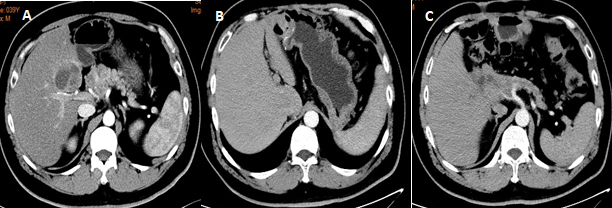

对于晚期胰腺神经分泌肿瘤,手术治疗仍然是重要的治疗手段之一。如果转移病灶和原发病灶都可切除,推荐行原发灶联合转移灶的根治性切除。如果无法根治性切除,部分合并肝转移的患者可以通过减瘤手术达到降低肿瘤负荷、改善肿瘤相关症状并改善患者预后的目的(图9)。减瘤手术的指证包括原发灶可切除、肿瘤分级为G1/G2、至少减瘤70%且有足够的剩余肝体积、无其他手术禁忌症。

图9 38岁男性患者,胰头神经内分泌肿瘤(G2)伴单发肝转移(A),2014年3月行胰十二指肠切除术+肝转移灶切除,术后病理提示pNET G2,ki67 5%,术后长效奥曲肽辅助治疗,目前肿瘤未复发(B,C)。